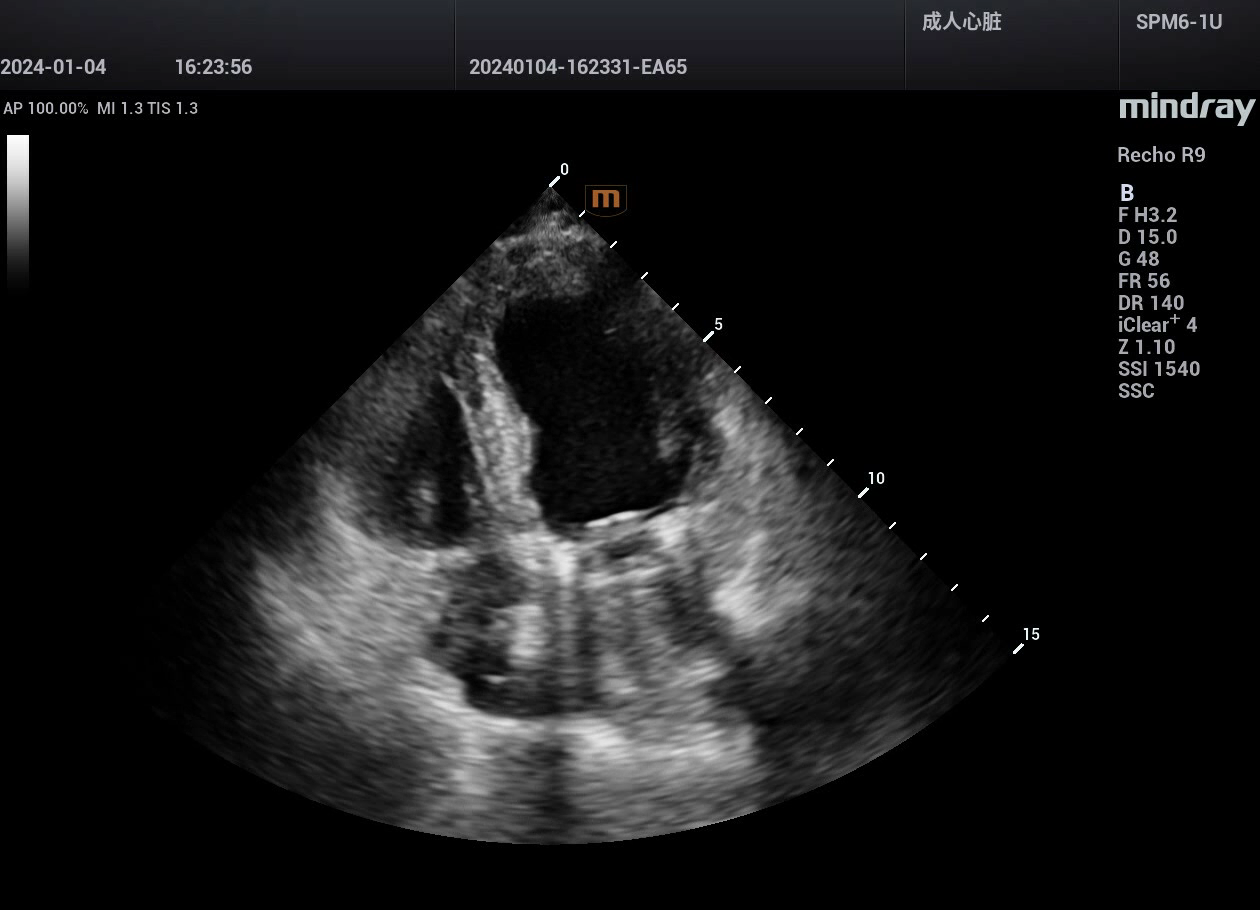

病例,急性心肌梗死,并发室间隔穿孔,迈瑞心脏彩超鲲鹏Recho R9,2024年5月

来源玉林市第一人民医院超声科,迈瑞超声鲲鹏实现超声事业高质量发展